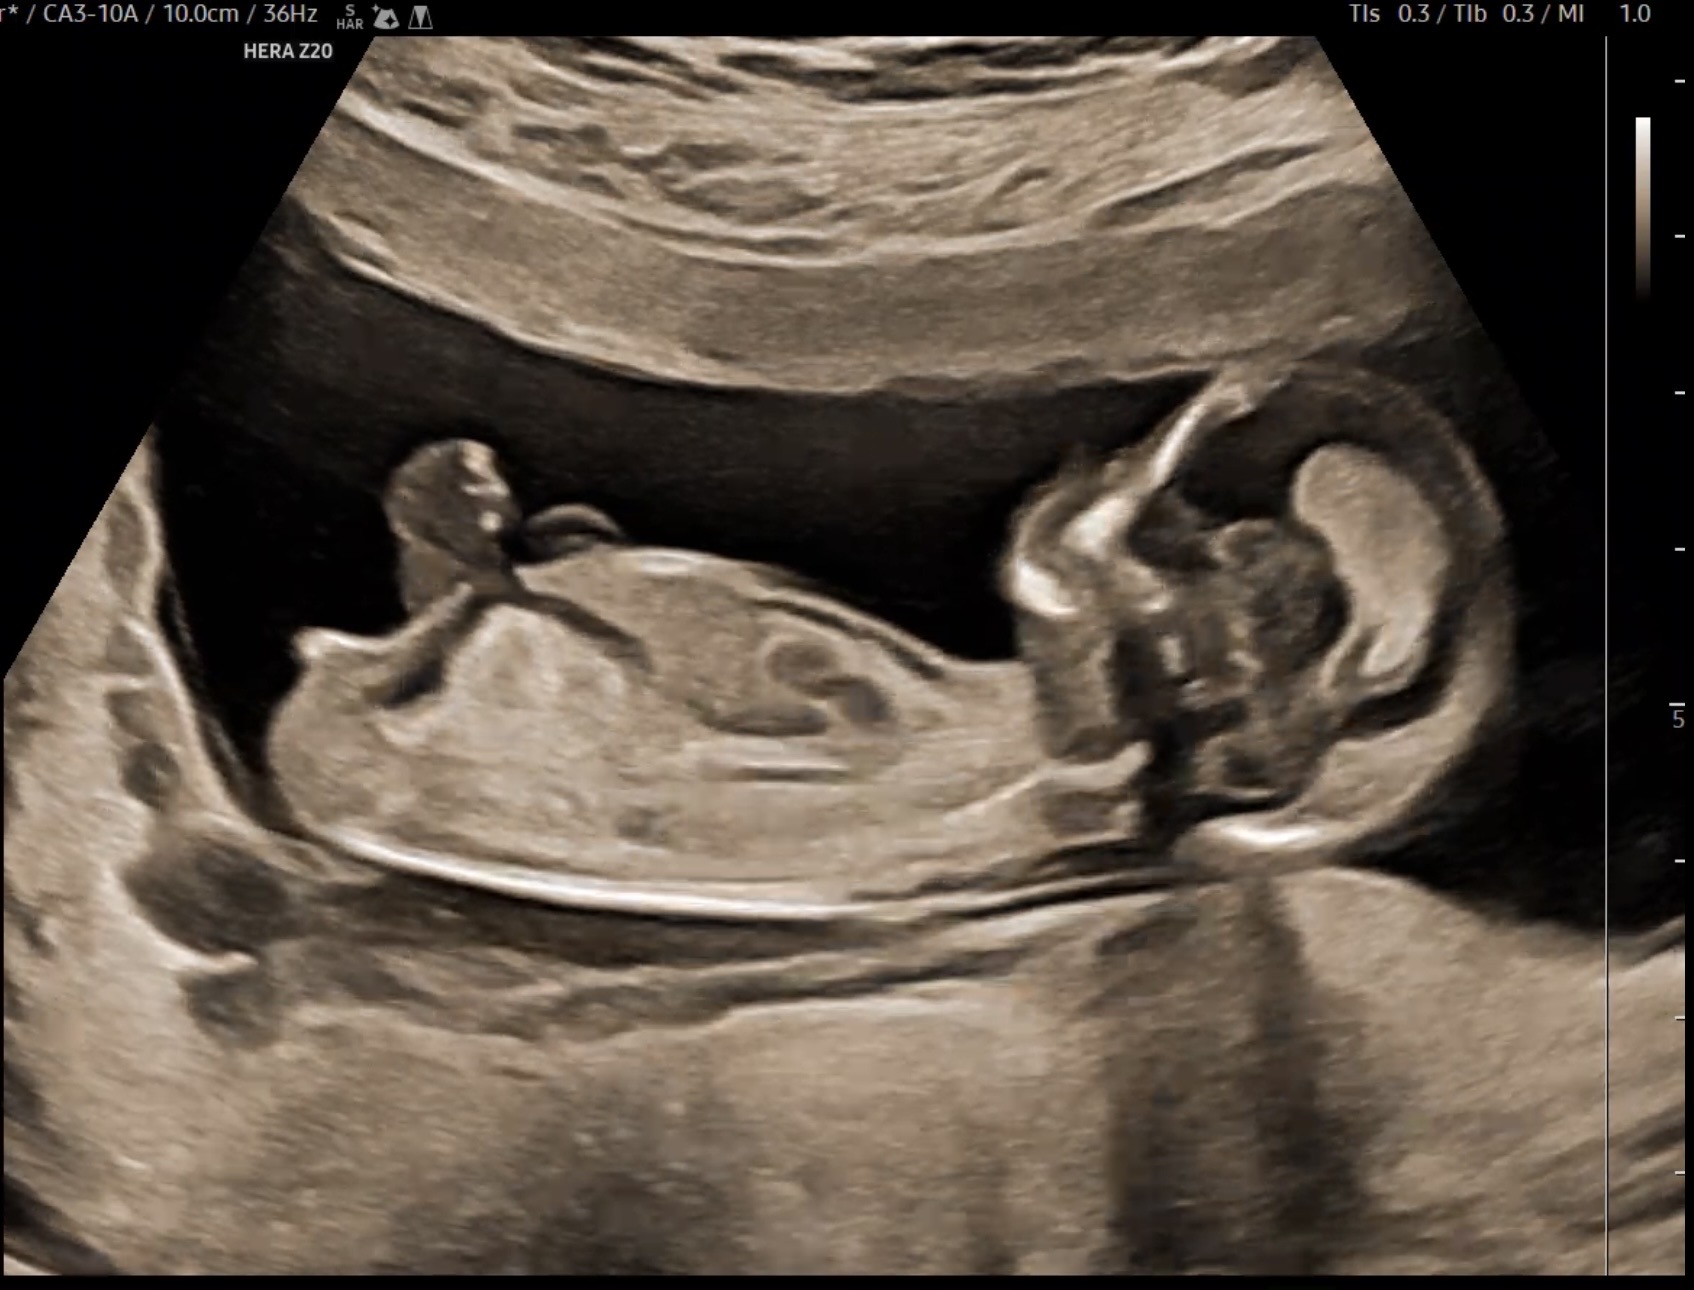

Hej dziewczyny...widzicie plec? Lekarka twierdzi, że 99% dziewczynka....? 12+4 z OM, 13+5 z USG.

Nie jestem lekarzem, a skoro lekarz jest pewien na 99% to raczej ciężko o pomyłkę… chociaż wg tego zdjęcia wychodzi chłopak 😂 córka miała podobne zdjęcie do Twojego w 12tc, synkowi bardziej wystawał wyrostek do góry.

Zapłaciłam za analizę lekarza online 😅.

Zobacz załącznik 1737137

Poważnie chciało Ci się za to płacić? 🙈 to dalej jest zgadywanka. Twoja lekarka mówi na 99%, tu Ci powiedzieli na 87%, błagam powiedz, ze to były jakieś grosze 🤣

Generalnie na takim etapie jedyny pewniak to badanie nipt. Cała reszta to naprawdę totalna zgadywanka, która może się potwierdzić, ale nie musi.